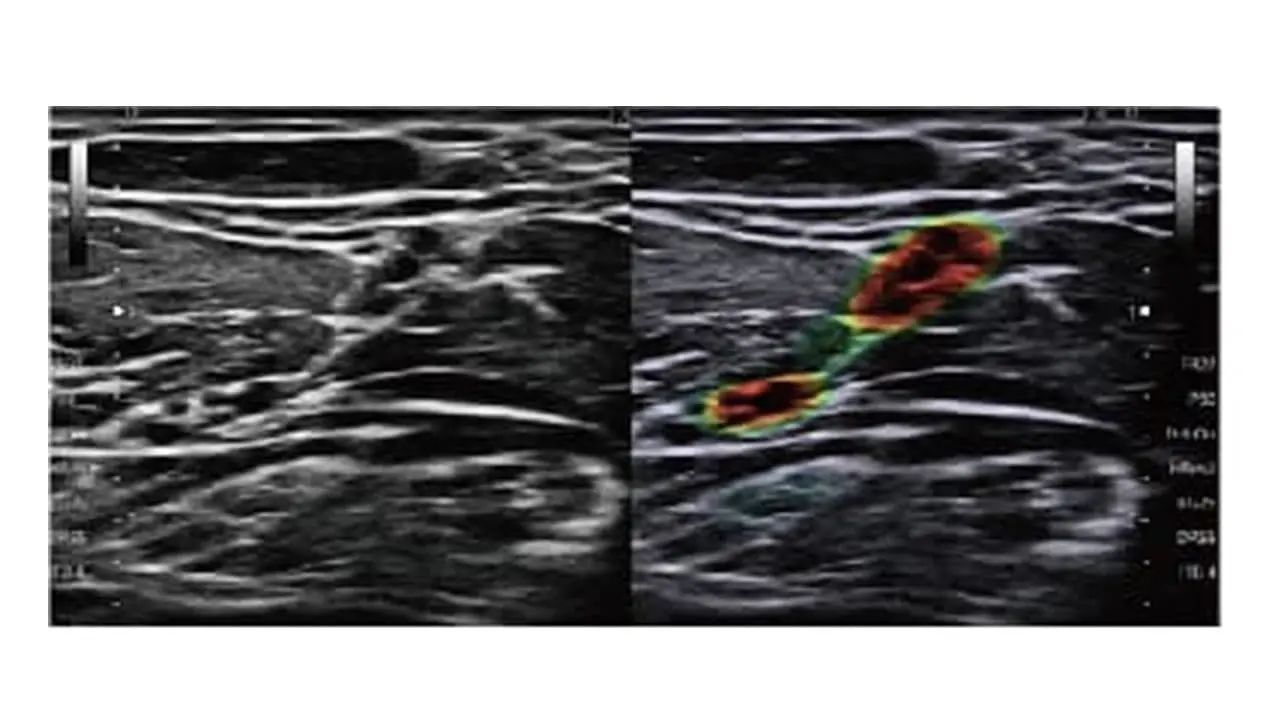

USソリューション

シンプルな検査フローと簡単な操作性で診察室でのスムーズな超音波検査を支援

・シンプルな操作性と高画質を両立

高感度広帯域プローブ(L11-3)

浅部の描出改善と深部の視認性を両立。

プレミアムクラスに迫る画質を実現。

USソリューション

シンプルな検査フローとハイレベルな診療をサポート

・シンプルな操作性と高画質を両立

高周波広帯域プローブX20L

浅部から深部まで音響ノイズ影響の少ない均一な画像の描出を可能にし、プローブ1本で幅広い検査に使用できます。

神経を可視化する VisNerve®

簡便かつ容易に神経を認識できるVisNerveは、処置時間の短縮をサポートします。